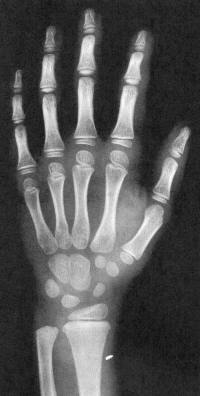

Sexo Masculino

6 anos

7 anos